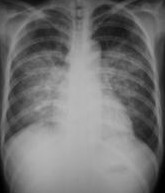

肺水肿间质期的X线表现主要为肺血管纹理模糊,增多,肺门阴影不清,肺透光度降低,肺小叶间隔增宽。两下肺肋膈角区可见与胸膜垂直横向走行的KerleyB线,偶见上肺呈弧形斜向肺门较KerleyB线长的KerleyA线。肺泡水肿主要表现为腺泡状致密阴影,呈不规则相互融合的模糊阴影,弥漫分布或局限于一侧或一叶,或从肺门两侧向外扩展逐渐变淡成典型的蝴蝶状阴影。有时可伴少量胸腔积液。但肺含量增加30%以上才可出现上述表现。CT和核磁共振成像术可定量甚至区分肺充血和肺间质水肿,但费用昂贵。

- 分布和形态呈多样性,可呈中央型、弥漫型和局限型。中央型表现为两肺中内带对称分布的大片状阴影,肺门区密度较高,形如蝶翼称为蝶翼征。局限型可见于一侧或一叶,多见于右侧。除片状阴影外,还可呈一个或数个较大的圆形阴影,轮廓清楚酷似肿瘤。

- 动态变化:肺水肿最初发生在肺下部、内侧及后部,很快向肺上部、外侧及前部发展,病变常在数小时内有显著变化。